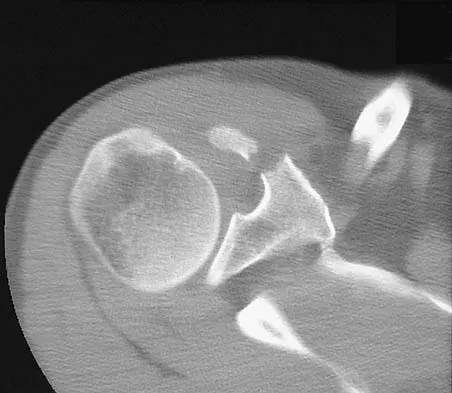

A paraplegic 32-year-old man was pulling himself up in bed by grasping the headboard rails when he felt a pop and immediate pain. A radiograph and CT scan are shown in Figures 2a and 2b. Based on these findings, management should consist of

Explanation

The coracoid process is an essential component of the superior shoulder suspensory complex and must be maintained. Open reduction and internal fixation is recommended if the fragment is large and displaced more than 1 cm. Froimson AI: Fracture of the coracoid process of the scapula. J Bone Joint Surg Am 1978;60:710-711.